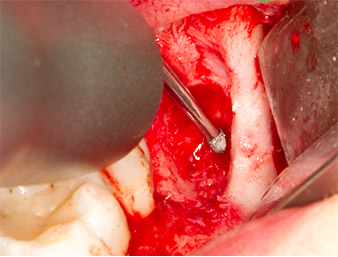

À l'aide d’un insert pour le débridement parodontal (Piezomed P1), l’espace ligamentaire parodontal de la racine résiduelle est ensuite élargi de manière minimale (Fig. 8).

Le même insert activé est inséré dans le canal radiculaire et détache le fragment sous l’effet de ses vibrations à micro-oscillations (Fig. 9, 10).

Piezomed P1

Fig. 9 : L’insert Piezomed P1 est recommandé par le fabricant essentiellement pour le débridement parodontal mais il est également adapté à la chirurgie. Ici, il est placé dans le canal radiculaire après élargissement minimal de l’espace ligamentaire parodontal.

Fig. 10 : Grâce à sa forme très affinée, l'insert peut pénétrer dans le canal radiculaire et extraire le reste radiculaire sous l’effet des micro-oscillations (vibrations).

Il est ensuite possible, grâce à l’insert P1, d’extraire en un seul geste le reste radiculaire d’environ six millimètres de long (Fig. 11).